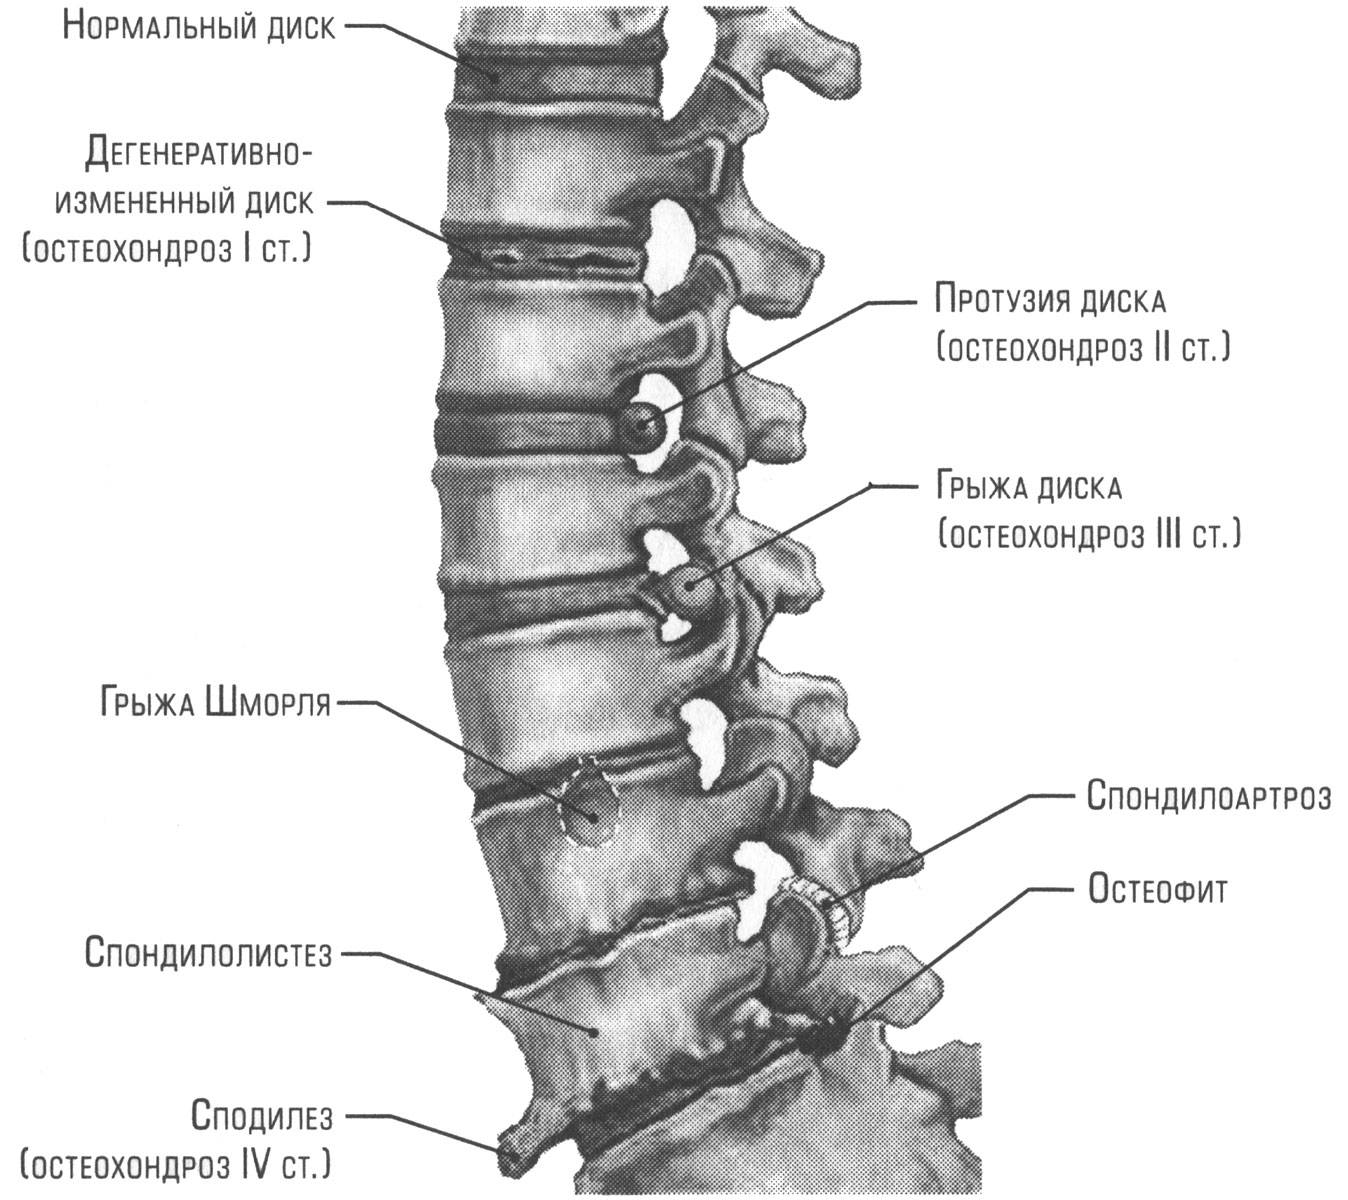

Позвонок Th10: анатомия и фото медицинских иллюстраций